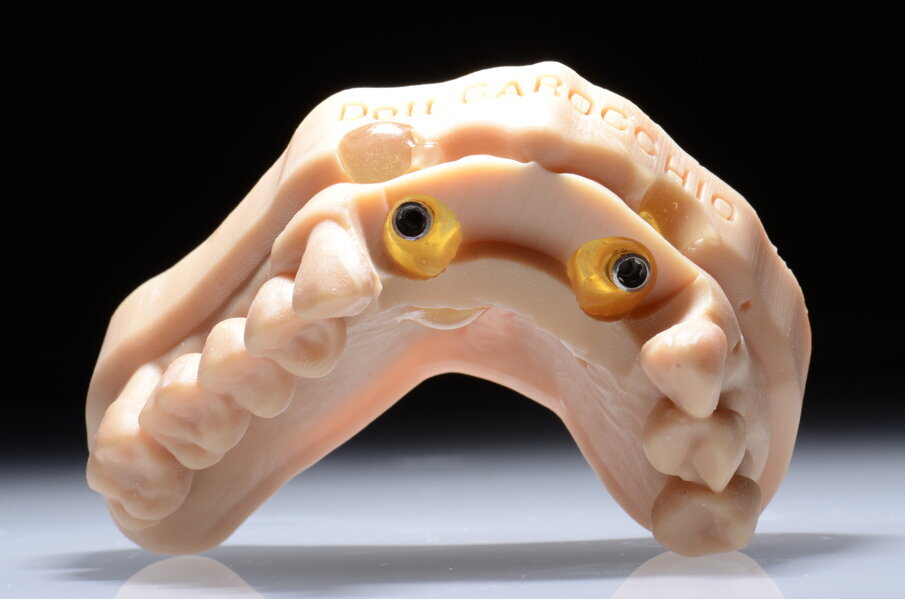

L’idea DIL (Digital Immediate Load) nasce da questa riflessione: se la dima viene alloggiata correttamente sul modello stereolitografico, e se la stessa viene utilizzata per inserire gli impianti allora possiamo pensare di utilizzare subito dopo il posizionamento implantare una seconda dima senza boccole (Sleeve) che chiameremo dima protesica. Subito dopo la chirurgia possiamo inserire attraverso gli spazi guidati i transfert da impronta sugli impianti e bloccarli con della resina alla dima stessa. In questo modo possiamo evitare di rilevare una nuova impronta (sia analogica che digitale) che ci costringerebbe a realizzare un nuovo modello e soprattutto a rilevare una nuova dimensione verticale specialmente nei casi di arcate edentule. Alla dima con i transfert bloccati vengono collegati gli analoghi. Questa unione tra dima protesica, transfert e analoghi degli impianti inseriti rappresenta il cuore della tecnica DIL. Infatti questo assemblato chirurgico-protesico viene riposizionato sul modello digitale master iniziale. Gli analoghi vengono a loro volta bloccati con della resina. Otteniamo così un modello master affidabile con la posizione corretta degli impianti (tecnica DIL). Questo tipo di approccio è stato in passato utilizzato con flussi analogici che avevano però un limite: il modello master ottenuto non era relazionabile all’antagonista e quindi si rendeva necessario un altro passaggio analogico per rilevare la nuova dimensione verticale8. Con la tecnica DIL, e quindi con un flusso tutto digitale il riposizionamento della dima protesica con i transfert sul modello master iniziale produrrà un modello master post chirurgico che avrà un duplice vantaggio, quello cioè di avere la posizione esatta degli impianti inseriti e quello di avere un’arcata già relazionata a quella antagonista (tecnica DIL). Sugli analoghi degli impianti, poi, vengono inserite le componenti secondarie scelte.

Alloggiamo la dima protesica (Fig. 33), e blocchiamo i transfert con della resina trasparente (tecnica DIL) (Figg. 34, 35). In questo modo possiamo far riposare il paziente in studio dopo appena 35 minuti dall’inizio dell’intervento. La dima protesica, infatti (Fig. 36) con i transfert inseriti viene completata con l’unione degli analoghi ai transfert (Fig. 37). L’insieme così composto viene riadattato sul modello master digitale iniziale (Figg. 38-40) sul quale era stata costruita sia la dima chirurgica che la dima protesica come anche il provvisorio. Gli analoghi vengono bloccati sul modello con resina trasparente (Figg. 41-43). Alloggiamo il provvisorio sul modello master digitale così ottenuto (Figg. 44, 45).

Il risultato sarà quello di ottenere un modello master già relazionato all’arcata antagonista e soprattutto un modello che contiene la posizione esatta degli impianti appena inseriti. Questo rappresenta il cuore della tecnica DIL, evitiamo impronta post-chirurgica, evitiamo la registrazione di una nuova dimensione verticale e realizziamo il modello di lavoro in pochissimo tempo.

Le fasi successive sono tecniche, uniamo la componente secondaria angolata a 17° programmata agli analoghi degli impianti (Figg. 46-49), su di essa avviteremo il moncone SRA (Figg. 50, 51). Alloggeremo il provvisorio sul modello (Fig. 52) e le alette di riposizionamento ci consentiranno di essere precisi. Unire il provvisorio alle componenti secondarie sarà a questo punto molto semplice con resina fotopolimerizzabile (Fig. 53). In poco più di un’ora abbiamo funzionalizzato il provvisorio (Figg. 54-57). Il montaggio del provvisorio avverrà collegando prima le componenti secondarie angolate agli impianti (Figg. 58, 59) e poi il provvisorio stesso (Figg. 60-70).

Il piano di trattamento prevede l’estrazione degli elementi dentali, l’inserimento di due impianti e la realizzazione di una protesi fissa di quattro elementi. Il problema da gestire è quello della fase provvisoria. Non è ipotizzabile una protesi mobile e quindi programmiamo di inserire subito dopo l’intervento un provvisorio immediato. Questo ci consente di condizionare da subito i tessuti periimplantari e anche le zone dei ponti. Si rileva un’impronta digitale (Figg. 5, 6), e la programmazione degli impianti viene effettuata con un software di chirurgia guidata (Fig. 7) e la posizione degli impianti nello spazio biologico e nello spazio protesico viene fatta sulla base di una ceratura diagnostica (Figg. 8, 9). Inseriamo gli impianti virtuali nell’osso disponibile (Figg. 10-13) e in relazione all’aspetto protesico correggiamo l’asse di inclinazione degli impianti con componenti secondarie angolate a 17° (Figg. 14, 15). Questo ci consentirà di realizzare una protesi avvitata con i fori situati nella zona palatale.